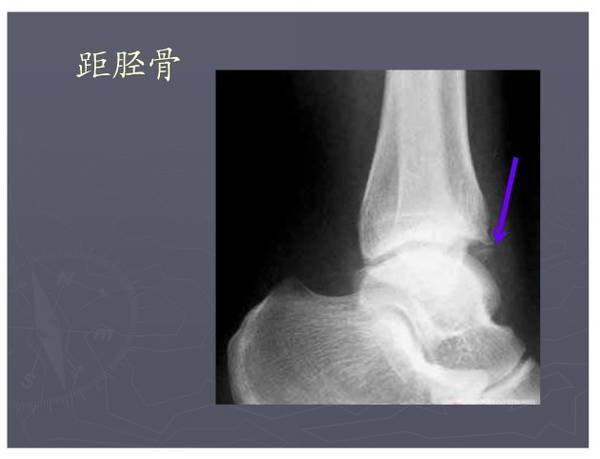

常见异常副骨或籽骨

在足部发生率最高,如副舟骨、距上骨、胫下骨腓小骨等